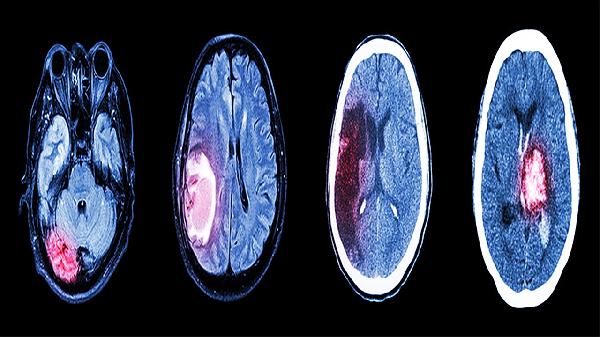

使用补脑安神片期间需保持情绪稳定,晚餐避免辛辣刺激食物,睡前1小时可配合温水泡脚。中成药见效较慢,症状持续2周未缓解或加重时,应及时到神经内科或睡眠门诊完善多导睡眠监测。记忆力减退患者建议同步进行脑电图和头部影像学检查,排除阿尔茨海默病等神经系统病变。青少年及儿童使用须严格遵医嘱,不可自行增减剂量。